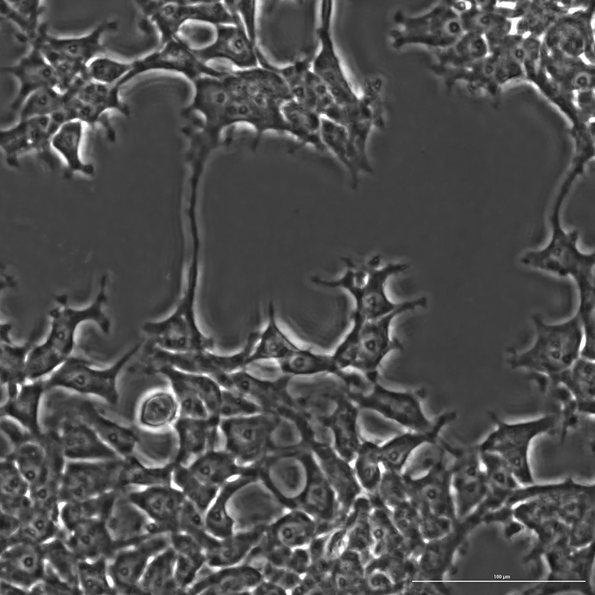

(사진=프로플루언트) OpenCRISPR-1에 의해 편집된 인간 세포

오픈크리스퍼(OpenCRISPR-1)를 통해 CRISPR 제품군의 우주를 확장하고 더 구축할 수 있는 기초 분자를 출시함으로써 이러한 AI 응용 프로그램은 유전자 편집 치료에 대한 접근성을 높이고 비용을 절감이 가능할 것이라고 밝혔다.